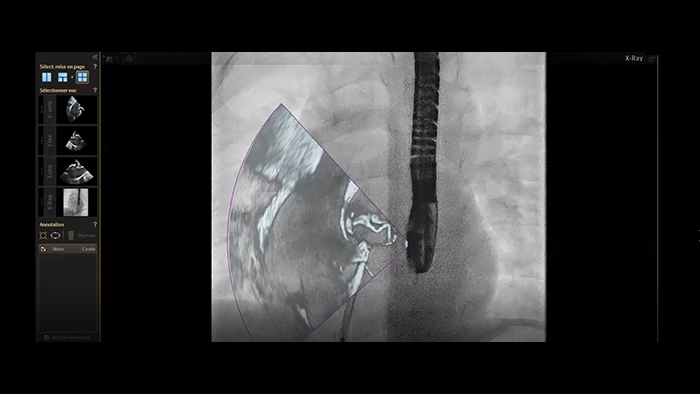

Fecho de ASD com fusão em tempo real EchoNavigator